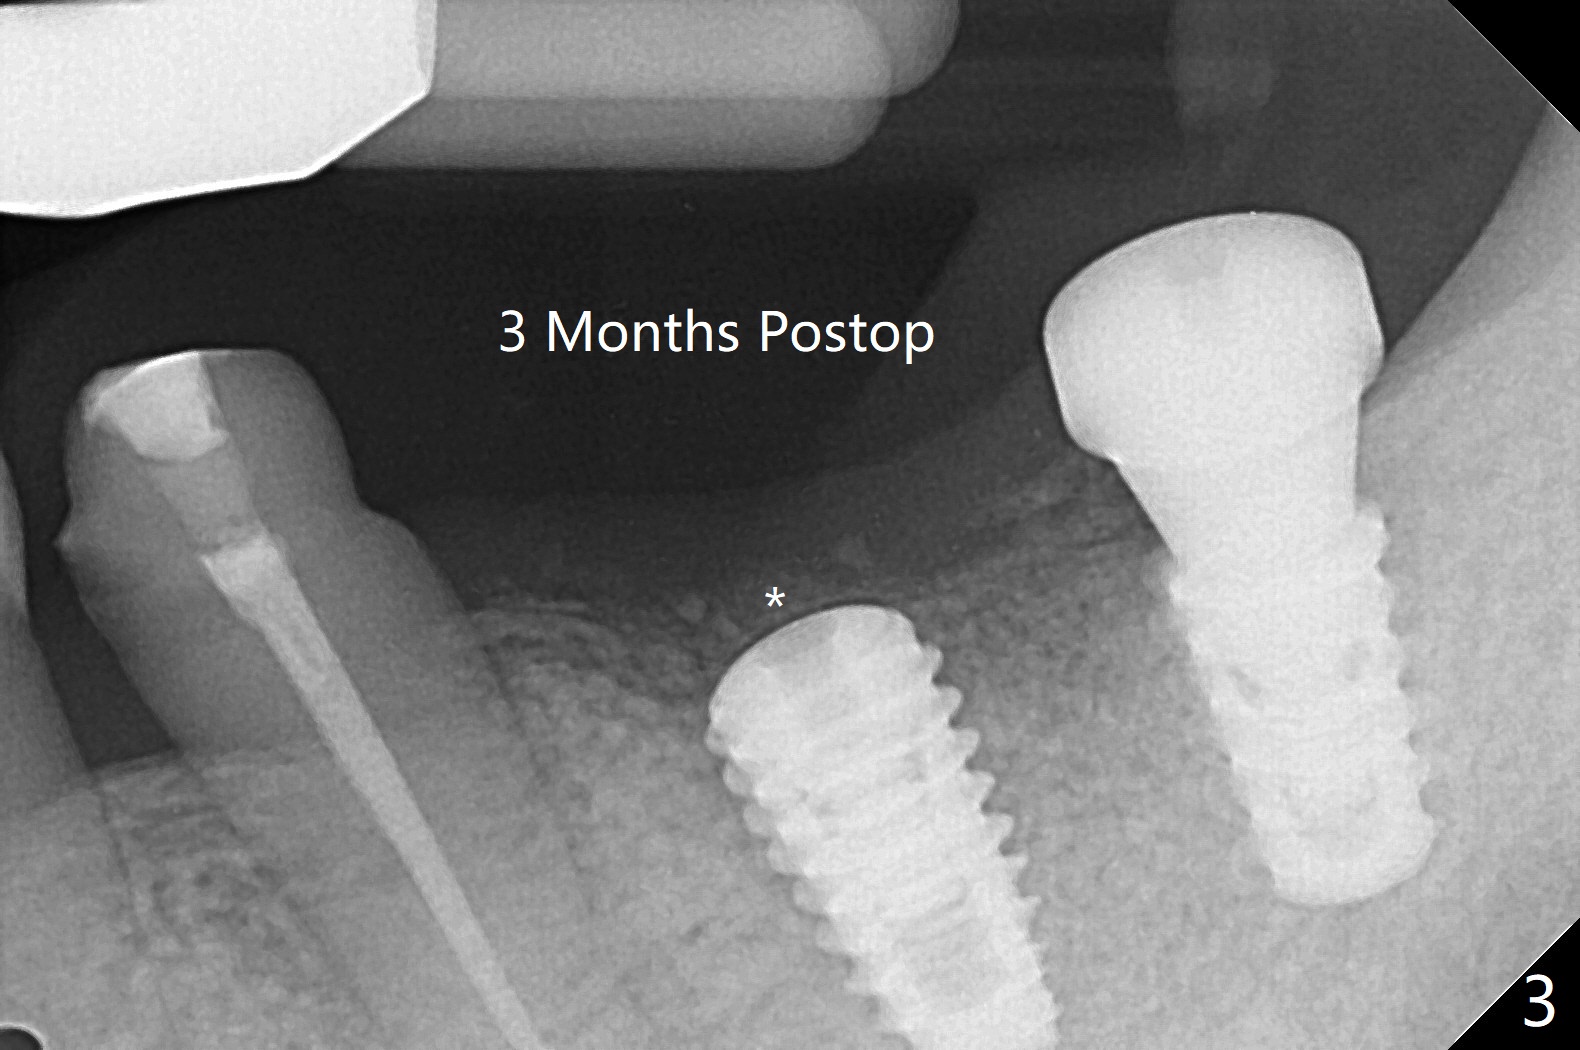

18,19导板远中架在17号牙残根表明树脂(图二:S),起到防止下沉作用,18号牙植体(~35Ncm)使用植体固定钉(fixture anchor mount no stop)植入,后者并且起着固定导板作用,增加19号牙植体植入稳定性,术中根尖片(图一)显示19号牙钻洞还不够深,之后钻头增加长度1.5毫米,4.5x8.5毫米植体扭力15-20Ncm(图二),但是与下齿槽神经管(红色虚线)还有很大距离,可能导板没有完全就位,植入后应该马上再次拍摄根尖片证实植入深度。由于18号牙区角化龈特别狭窄,切开种植,另外一个好处是容易植骨,但是术后疼痛明显,与上前牙即刻植牙(无切开)相比。今后尽量多做即刻种植。不过术后3个月包埋的植体表面有骨质覆盖(图三:*),二期手术很难找到愈合帽,而早些种植的上前牙植体由于过早受力,愈合不佳。当修复基台平面朝向颊侧,基台没有完全就位(图四:>)。当平面面对远中(图五:D),基台好像就位。